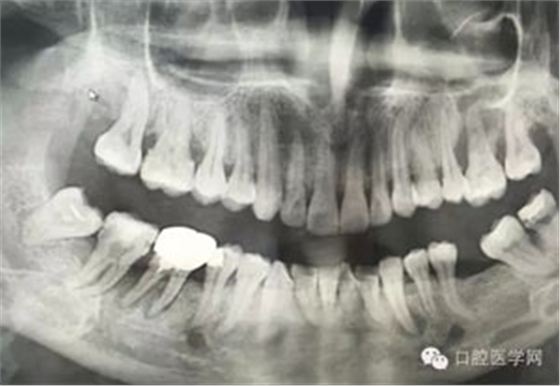

病例1:患者迫切希望保留自己的這一顆牙齒,根尖周陰影比較大,二度松動(dòng).而且旁邊有種植修復(fù)體,和患者溝通好后,治療好后觀察一個(gè)月后冠修復(fù),因?yàn)橛蟹N植的后期修復(fù),所以有了機(jī)會(huì)觀察,術(shù)后三個(gè)月和術(shù)后四個(gè)月,根尖恢復(fù)的還算不錯(cuò),希望能夠繼續(xù)觀察下去.這樣子的病例,做的時(shí)候我們一定要非常的小心,和患者要有充分的溝通以及不同科室的溝通然后決定怎么樣做比較好,假如就是出現(xiàn)了問題,到時(shí)候我們也比較好處理些,免得我們自己到時(shí)候不好收?qǐng)觥?/span> 病例2:364647中齲的樹脂充填,現(xiàn)在樹脂的充填材料非常之多,有些時(shí)候,我們感覺有了好的材料我們就可以做出好的修復(fù),可是這是在我們有扎實(shí)的基本功的基礎(chǔ)上的,我們可以沒有那么好的樹脂,那么多的顏色選擇,修復(fù)的那么的逼真,但是我們至少要恢復(fù)患者牙齒的功能,將腐質(zhì)去除干凈,薄壁弱尖消除掉,選擇好適應(yīng)癥,給患者以盡可能好的修復(fù)。 來源于KQ88